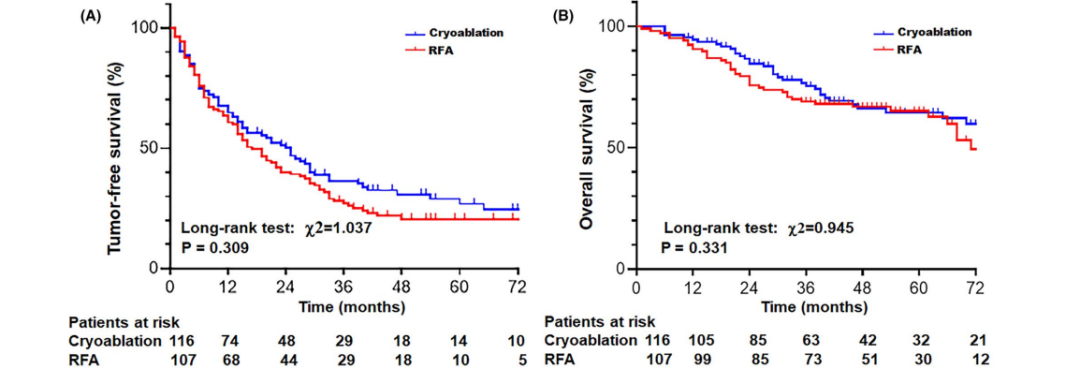

② 无肿瘤生存曲线和总生存曲线